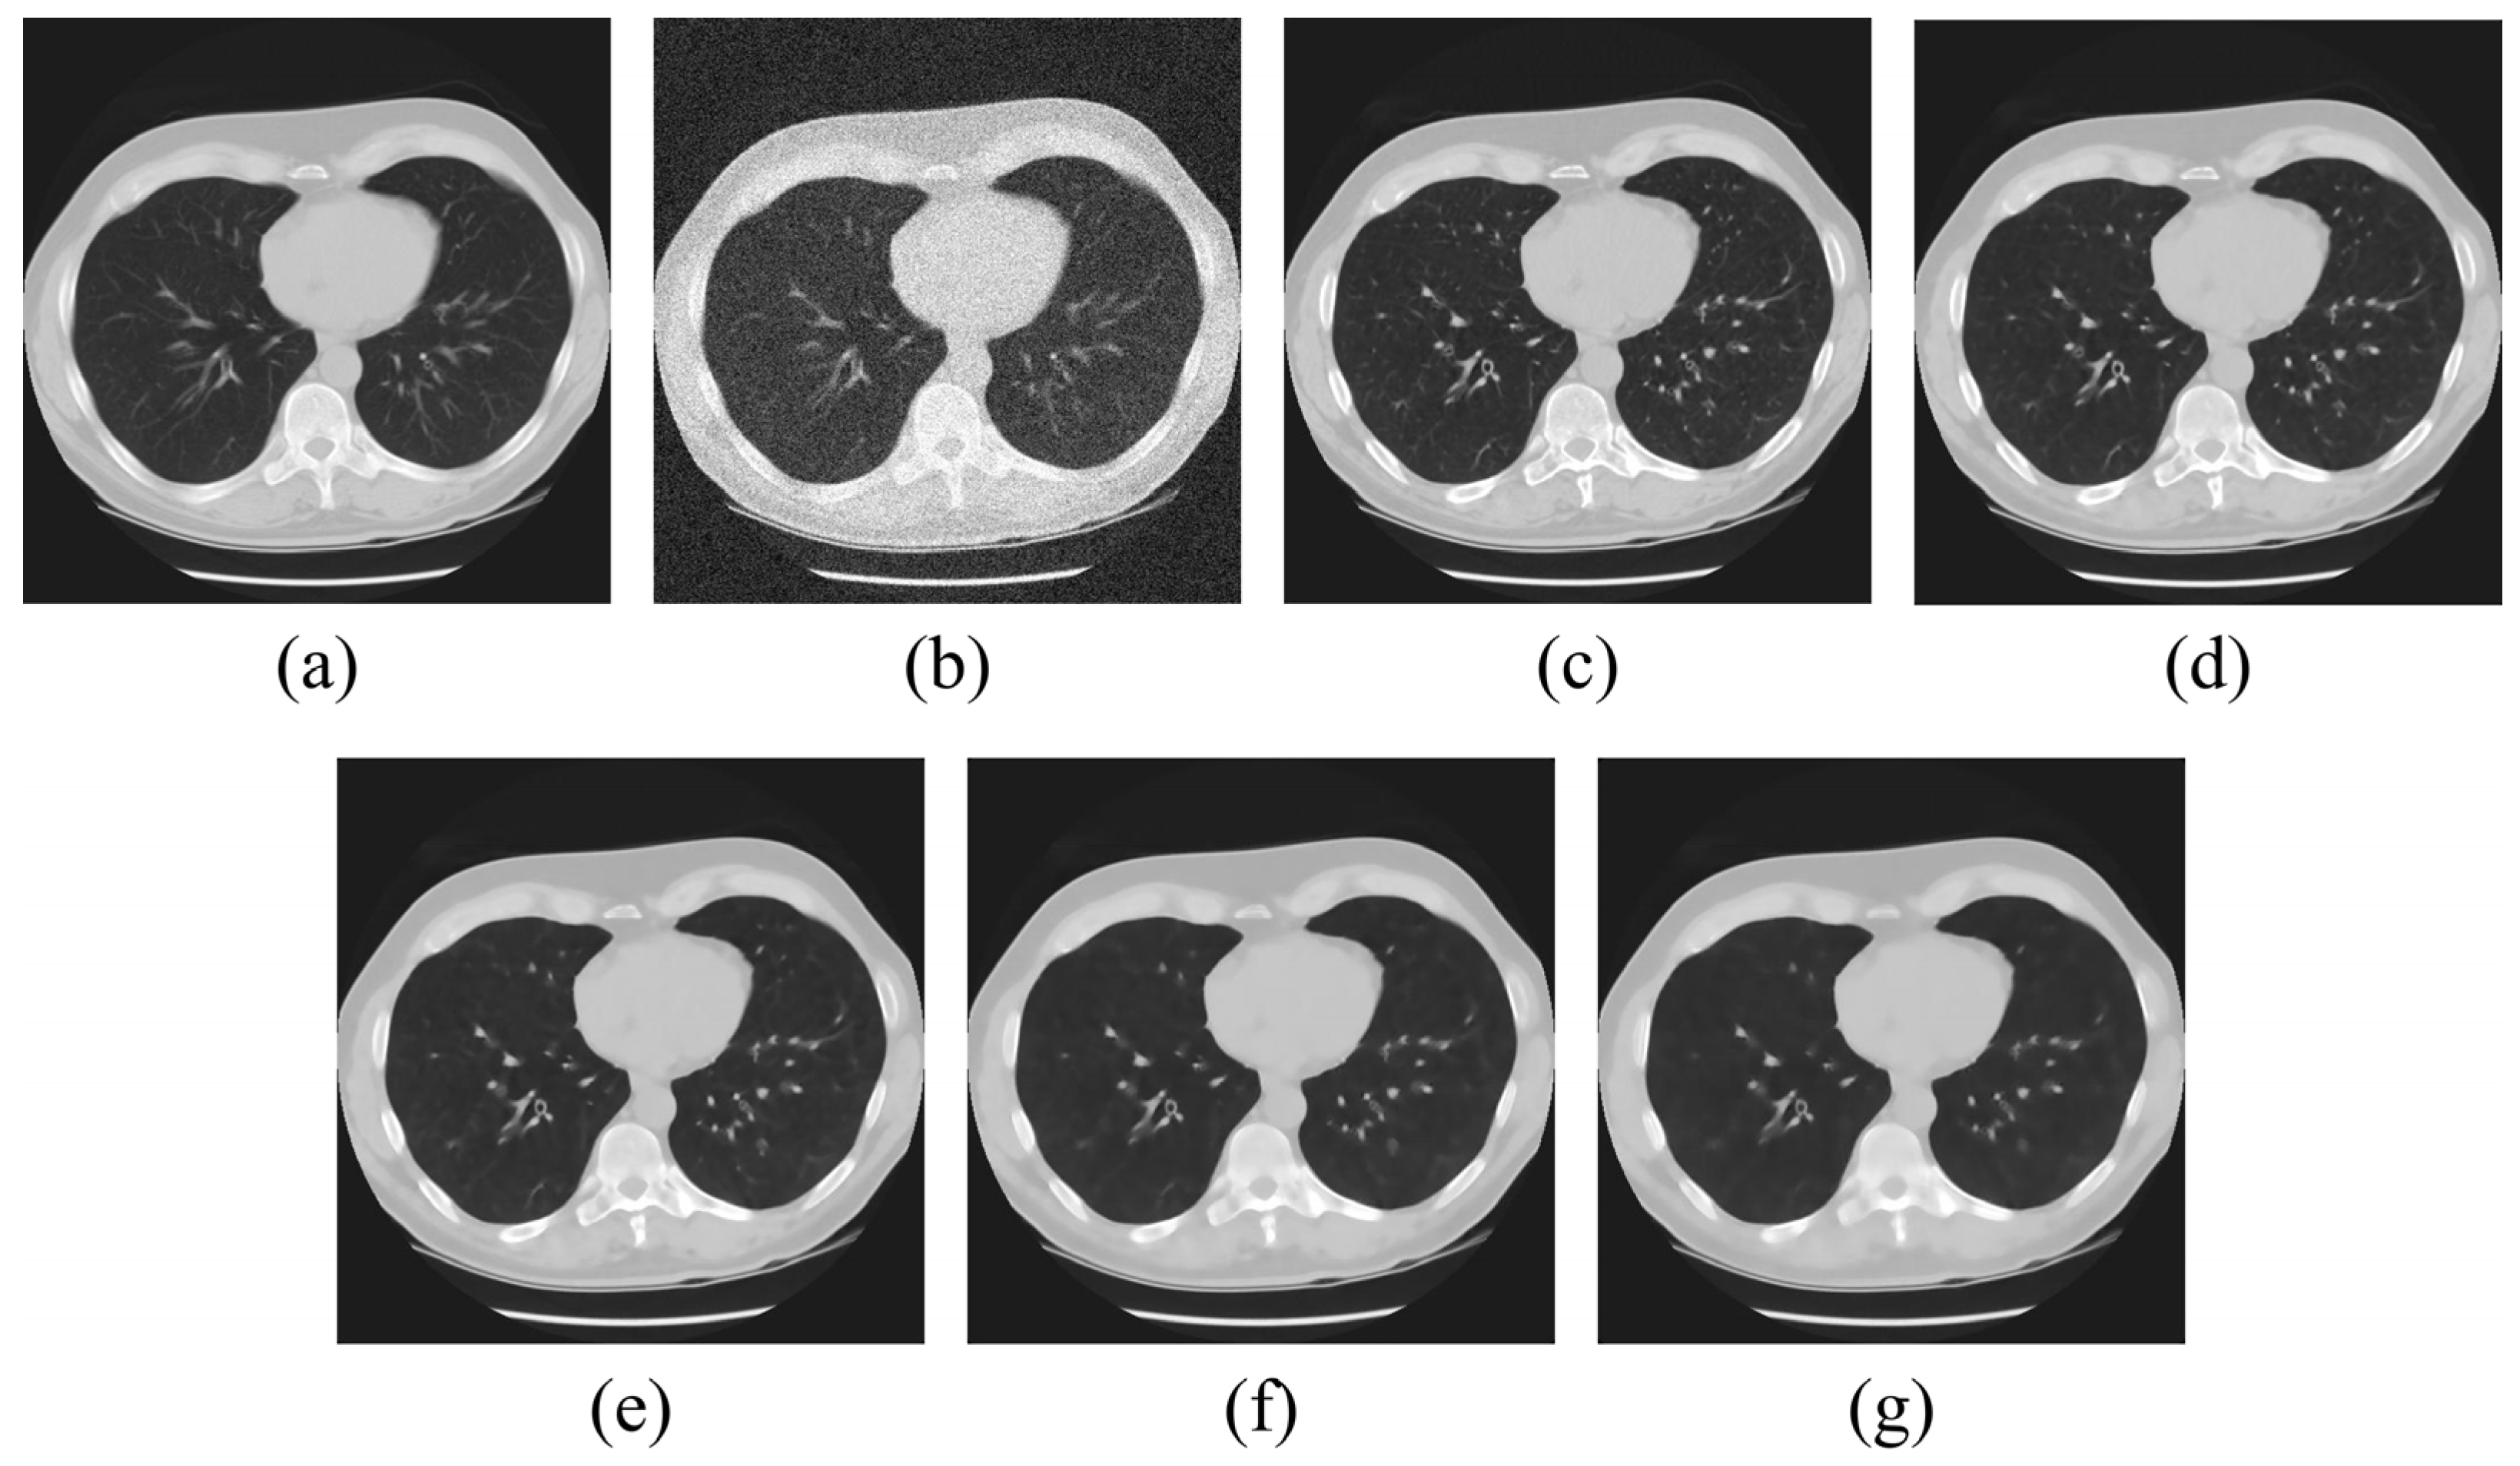

Gaussian noise was added to the standard lung CT image acquired using data from the NLST dataset, with MMWF kernel sizes of 3 × 3, 5 × 5, 7 × 7, 9 × 9, and 11 × 11. Figure 2 shows the MMWF applied to a lung CT image according to the kernel size, with Figure 2a as the ground-truth image and Figure 2b as the noisy image. The images from Figure 2c–g represent the application results of the MMWF with increasing kernel size.

Figure 2.

Filtered lung CT images with (a) original, (b) noisy, (c–g) 3 × 3 MMWF, 5 × 5 MMWF, 7 × 7 MMWF, 9 × 9 MMWF, and 11 × 11 MMWF.

After applying the MMWF by kernel size, a region-growing-based segmentation algorithm was used to perform lung segmentation. The results are shown in Figure 3, with Figure 3a as the ground-truth of segmented image and Figure 3b showing that the accuracy of segmentation has significantly deteriorated due to the presence of noise. From Figure 3c–g, the images demonstrate the segmentation results as a function of increasing the MMWF kernel size.

Figure 3.

Segmented lung image using region-growing-based segmentation algorithm with (a) original, (b) noisy, (c–g) 3 × 3 MMWF, 5 × 5 MMWF, 7 × 7 MMWF, 9 × 9 MMWF, and 11 × 11 MMWF.